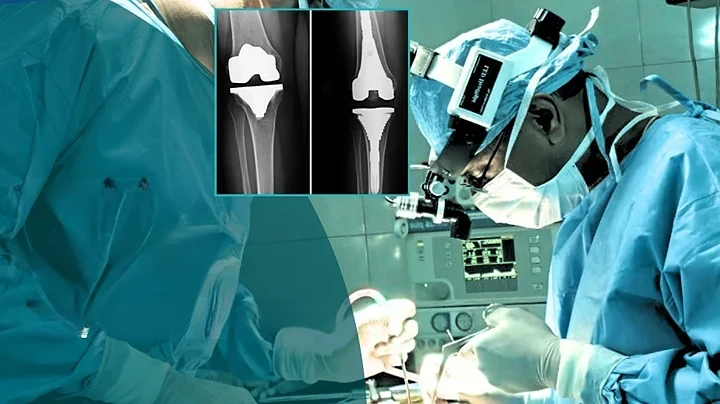

Advanced knee, hip, and shoulder replacement procedures performed with precision for long-term mobility and pain relief.

Primary Total Knee Replacement

Robotic Knee Replacement Surgery